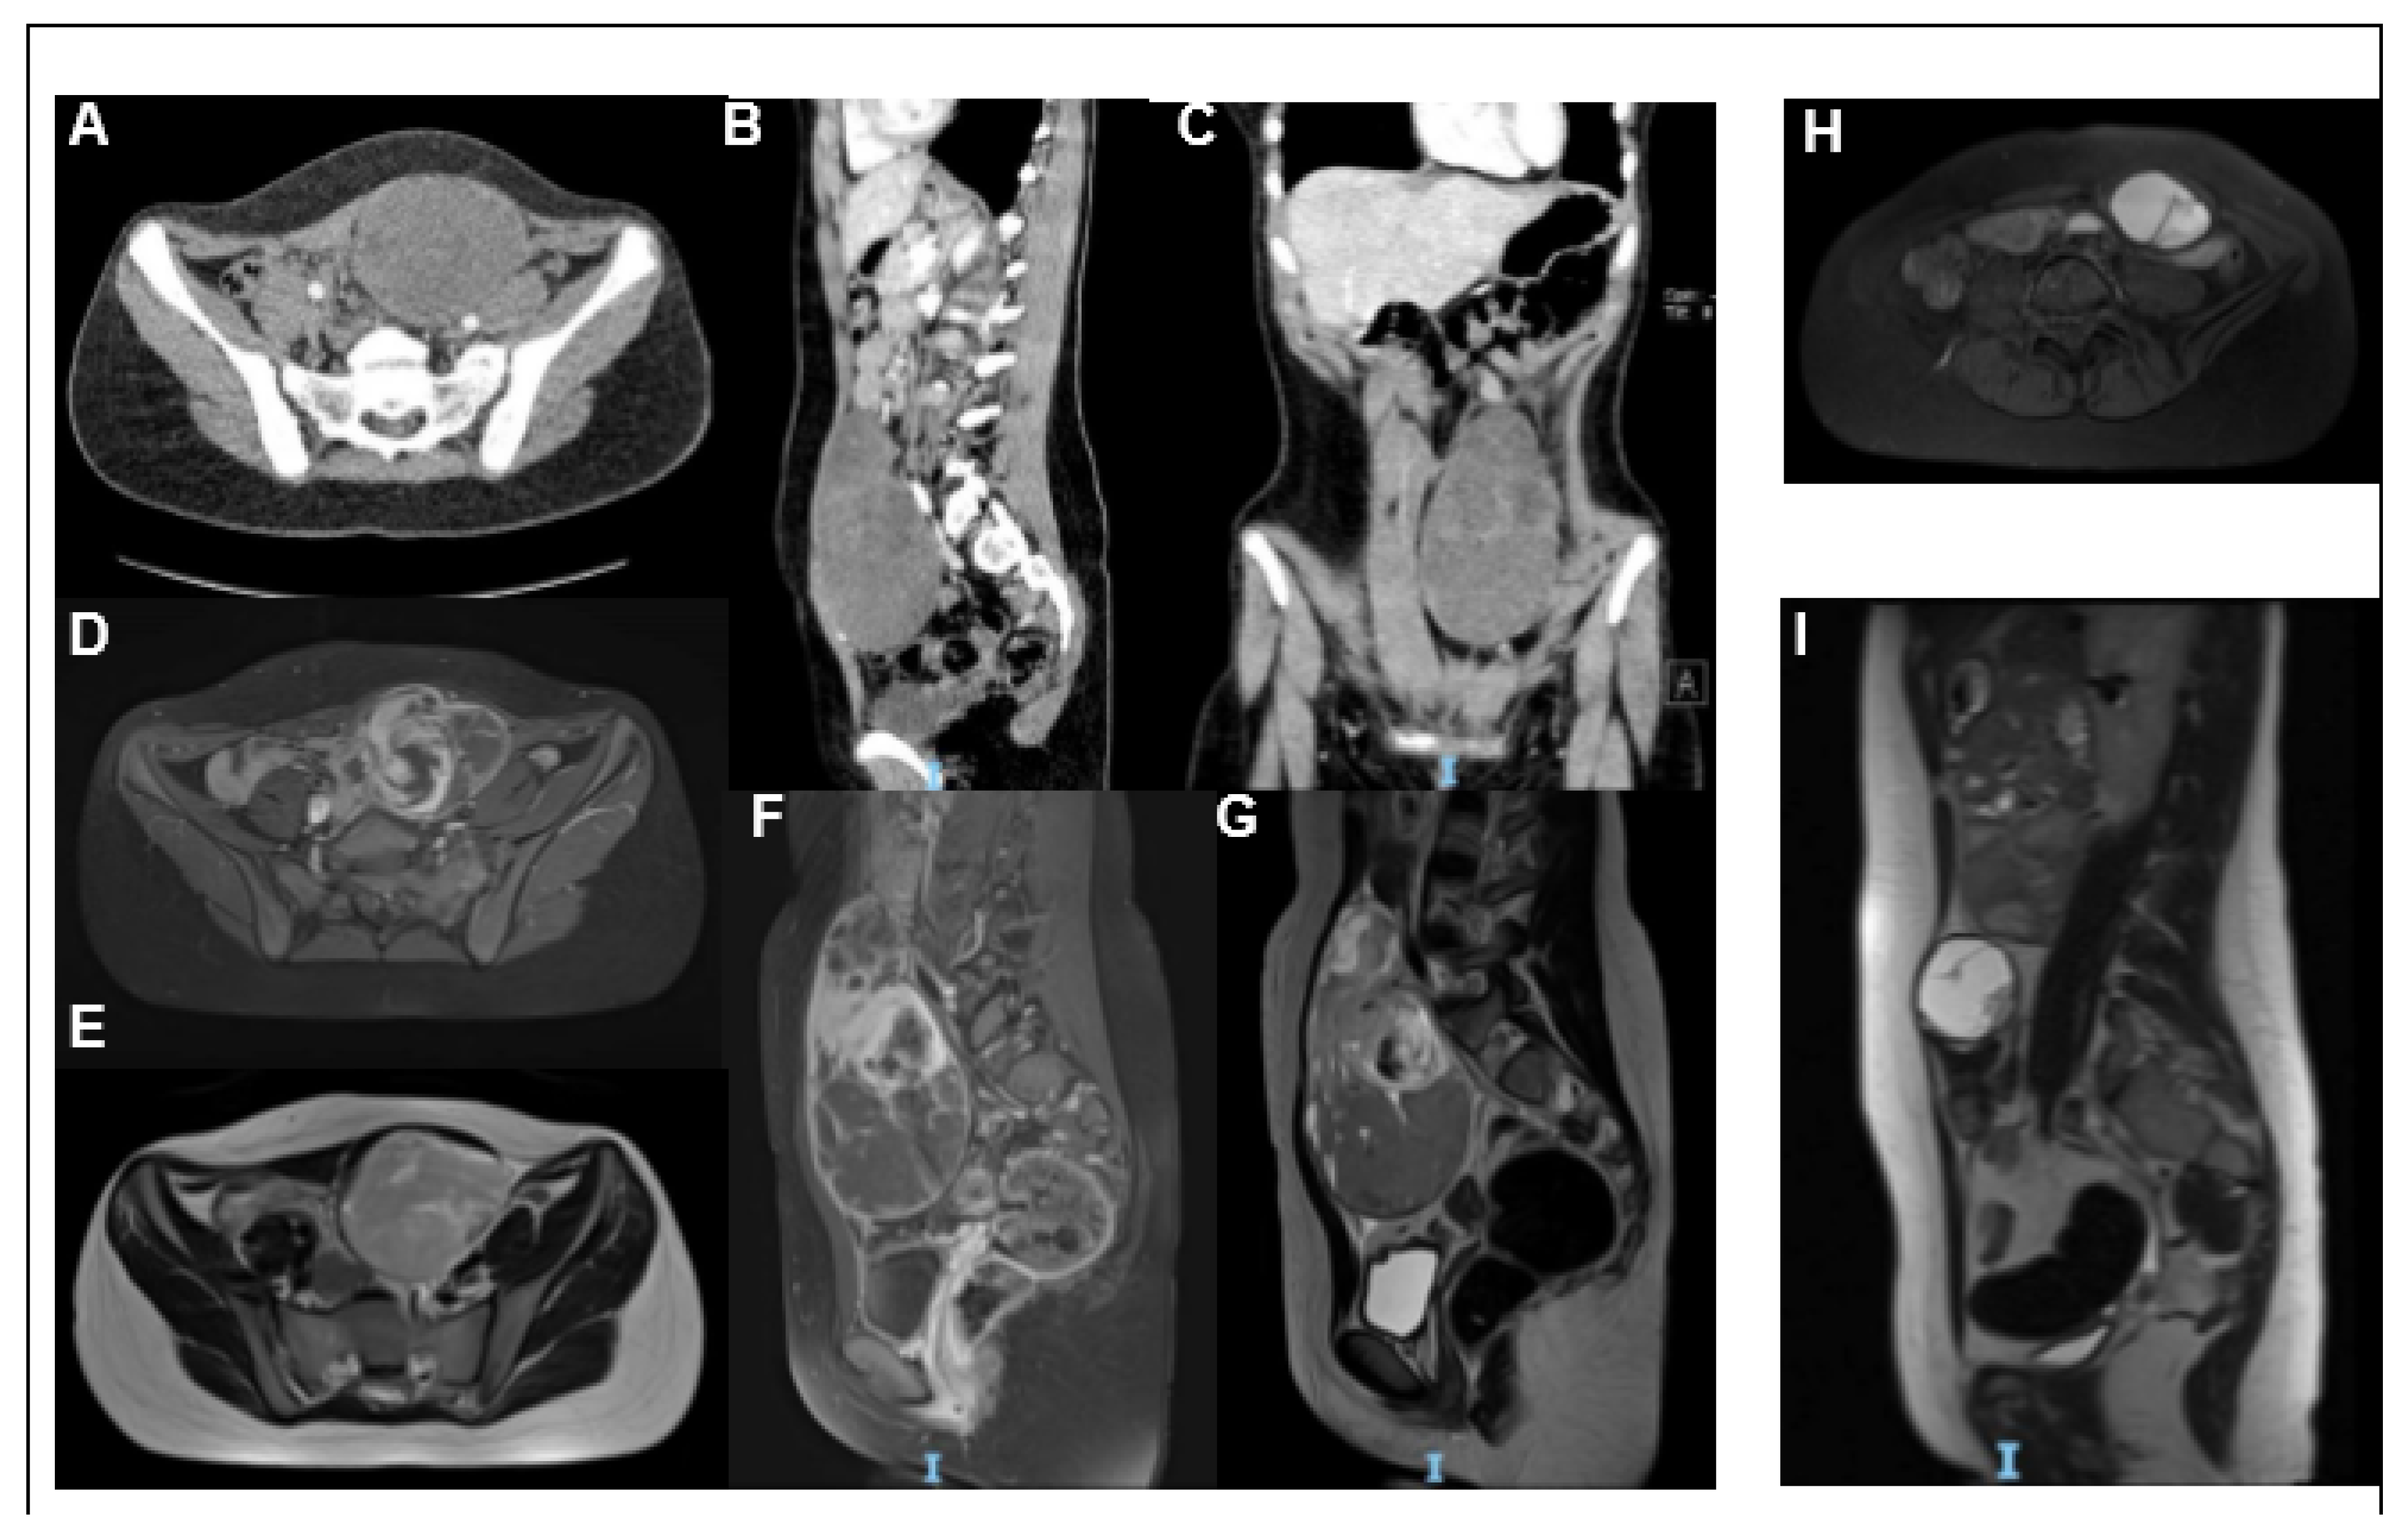

2. Case Report